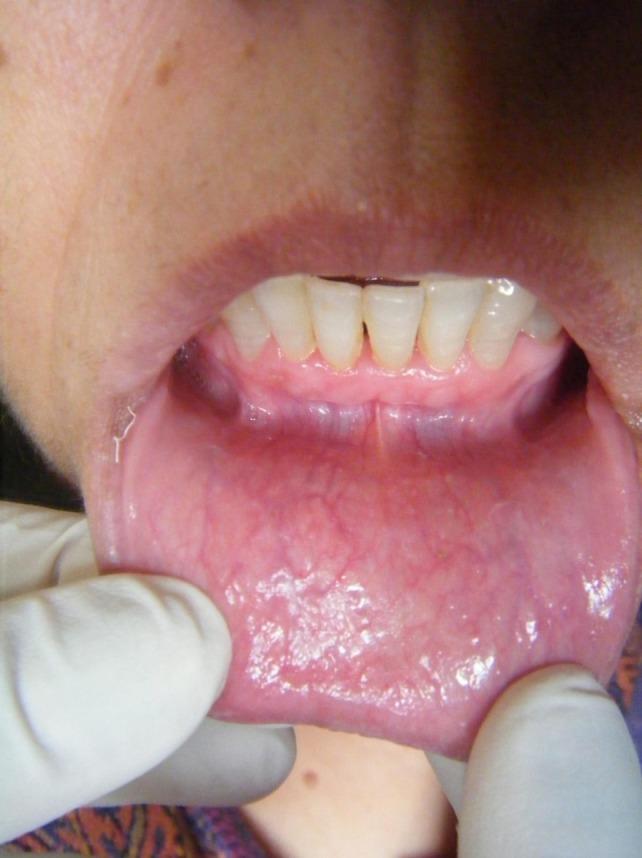

Burning mouth syndrome (BMS) is a relatively common disease that can severely affect the quality of life of the patient. It causes chronic orofacial pain or oral burning sensation even in the absence of any detectable organic cause. The etiology of BMS is complex and multifactorial. It has been associated with menopause, trigger events and even genetic polymorphisms. Although its etiology remains unclear, there is still much evidence that psychological elements like stress, anxiety or depression do play a significant role. There are several studies in the literature which only report the association of BMS with psychological factors. But to the best of our knowledge, there is no such case reported in the literature which has actually highlighted the management of such a case with psychogenic elements involved. In this case report, apart from discussing the role of psychological factors, the treatment of BMS with emphasis on counseling is also emphasized. Further, it is of interest to know that such patients with psychologically induced burning mouth syndrome have to be evaluated to their deepest details. Even their commonly overlooked gestures and habits like watching a particular television soap opera may be involved in their disease process. It can be concluded that psychological counseling in general dental practice can provide an effective cure for chronic oral burning sensation with psychological factors involved.